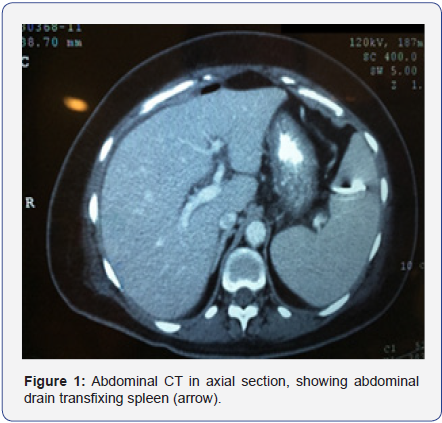

The patient remained hospitalized receiving a conservatory treatment associated with hyperbaric oxygen therapy, showing satisfactory and continuous improvement of her condition and a progressive reduction of the abdominal drain debit, with an improvement of the drained secretion aspect; regardless of showing mild pain on the left upper quadrant and occasional fever (she was receiving antibiotic therapy). She occasionally displayed sudden secretion elimination with a dark maroon color in the abdominal drain of the collecting bag along with a mild and transitory hypotension. The patient was, therefore, submitted to a new total abdomen CT scan (Figures 1 & 2), with the observation of an abdominal drain where its extremities were in the inferior spleen region, not to mention peripheral splenic hypotransparent areas; which may be related to infarct regions. Because of this, the patient was diagnosed with transfixing lesion of the spleen by the tubular drain.